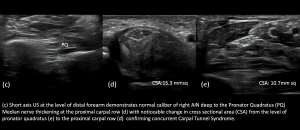

3.Anterior Interosseous Nerve (AIN) Pathology with pronator quadratus (PQ) atrophy

4.Anterior Interosseous Nerve with concurrent Carpal Tunnel Syndrome